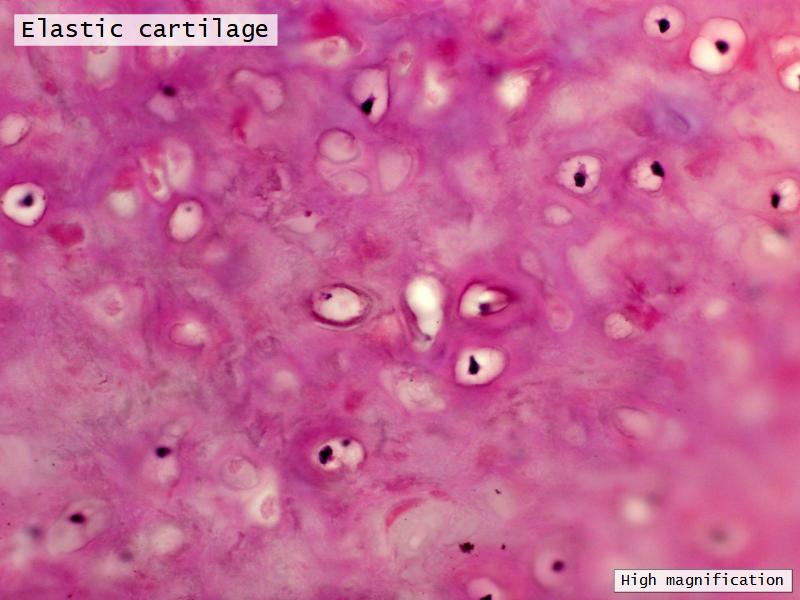

Trachea

Bronchi - Transitions

- Intrapulmonary bronchi

- Irregular cartilage